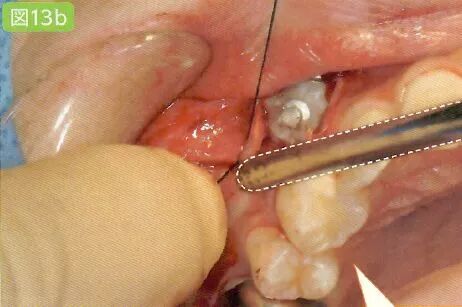

残根的拔除

通过拔除残根,将不需要削除牙槽骨,牙槽骨和牙根痊愈,也不会出现牙根膜腔根部肥大,根弯曲的症状。必然的牙槽骨和牙根之间是切削位置。留心同一部位的吸引。

刮匙怎么使用拔牙中吸唾器的使用技巧_https://www.jmylbn.com_新闻资讯_第22张